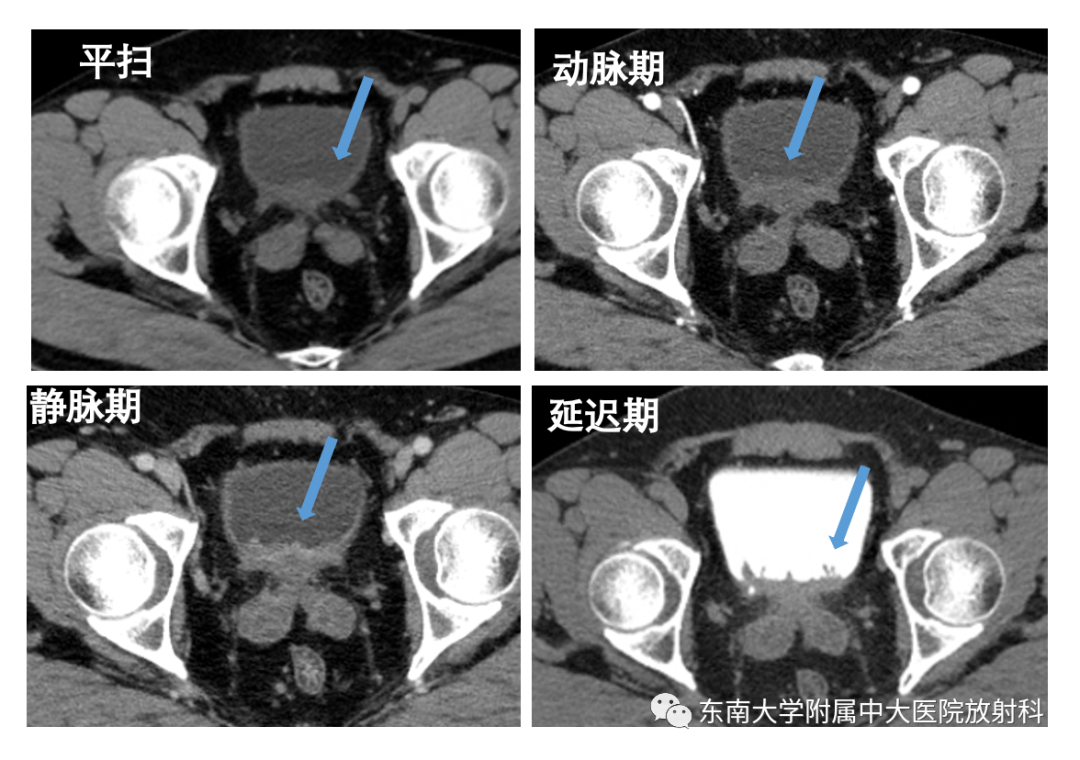

病例二

•男,40岁

•主诉:发现肉眼血尿1周

•现病史:患者于1周前无明显诱因下出现肉眼血尿,终末血尿,无尿痛,无发热、畏寒,无咳嗽、咳痰,无心慌心悸,无咯血,无睾丸疼痛,当时未予以重视及治疗,昨日发现血尿加重,来院就诊

2020-08-1 CTU 表现